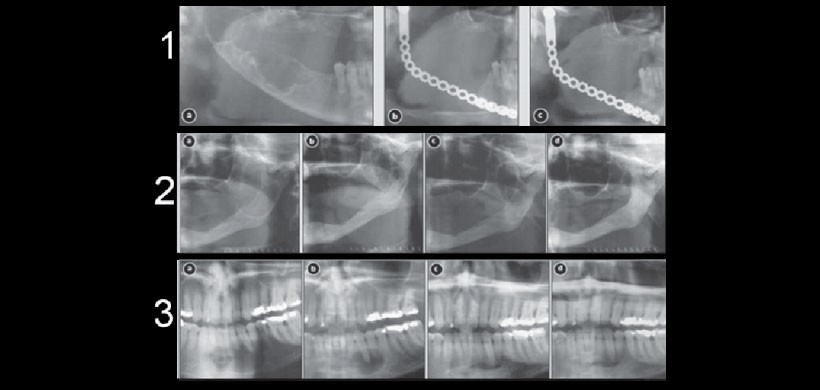

Figura 2: Opciones de tratamiento del TOQ (1) hemimandibulectomia, (2) marsupialización (3) enucleación y curetaje.